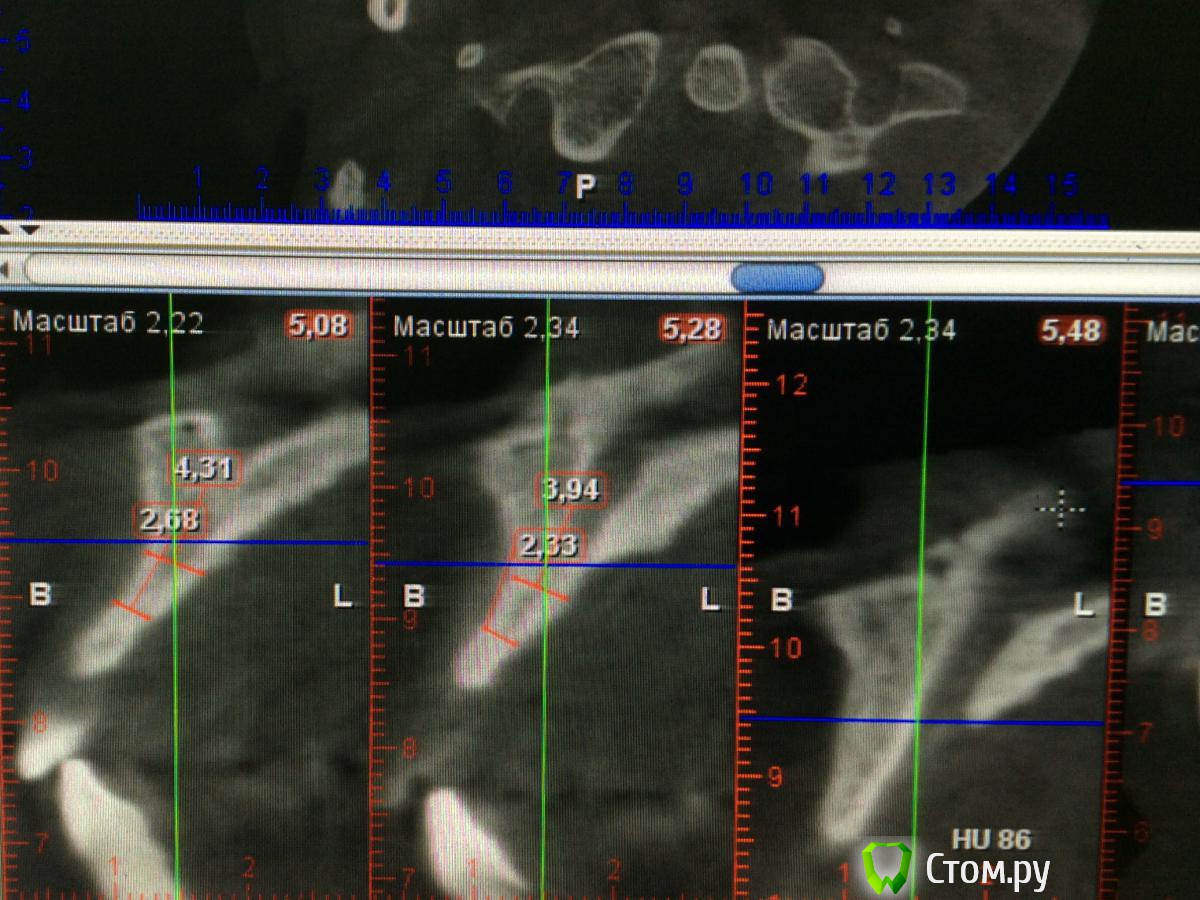

Chewey Опубликовано 23 июля, 2014 Поделиться Опубликовано 23 июля, 2014 (изменено) Какие варианты можно предложить ? Пациент 32 года, потерял 11,21. В следствии травмы, по высоте все неплохо, а вот объем в области 11. 2,6 мм , а в области 21,. 4.3мм. Изменено 23 июля, 2014 пользователем Chewey Ссылка на комментарий